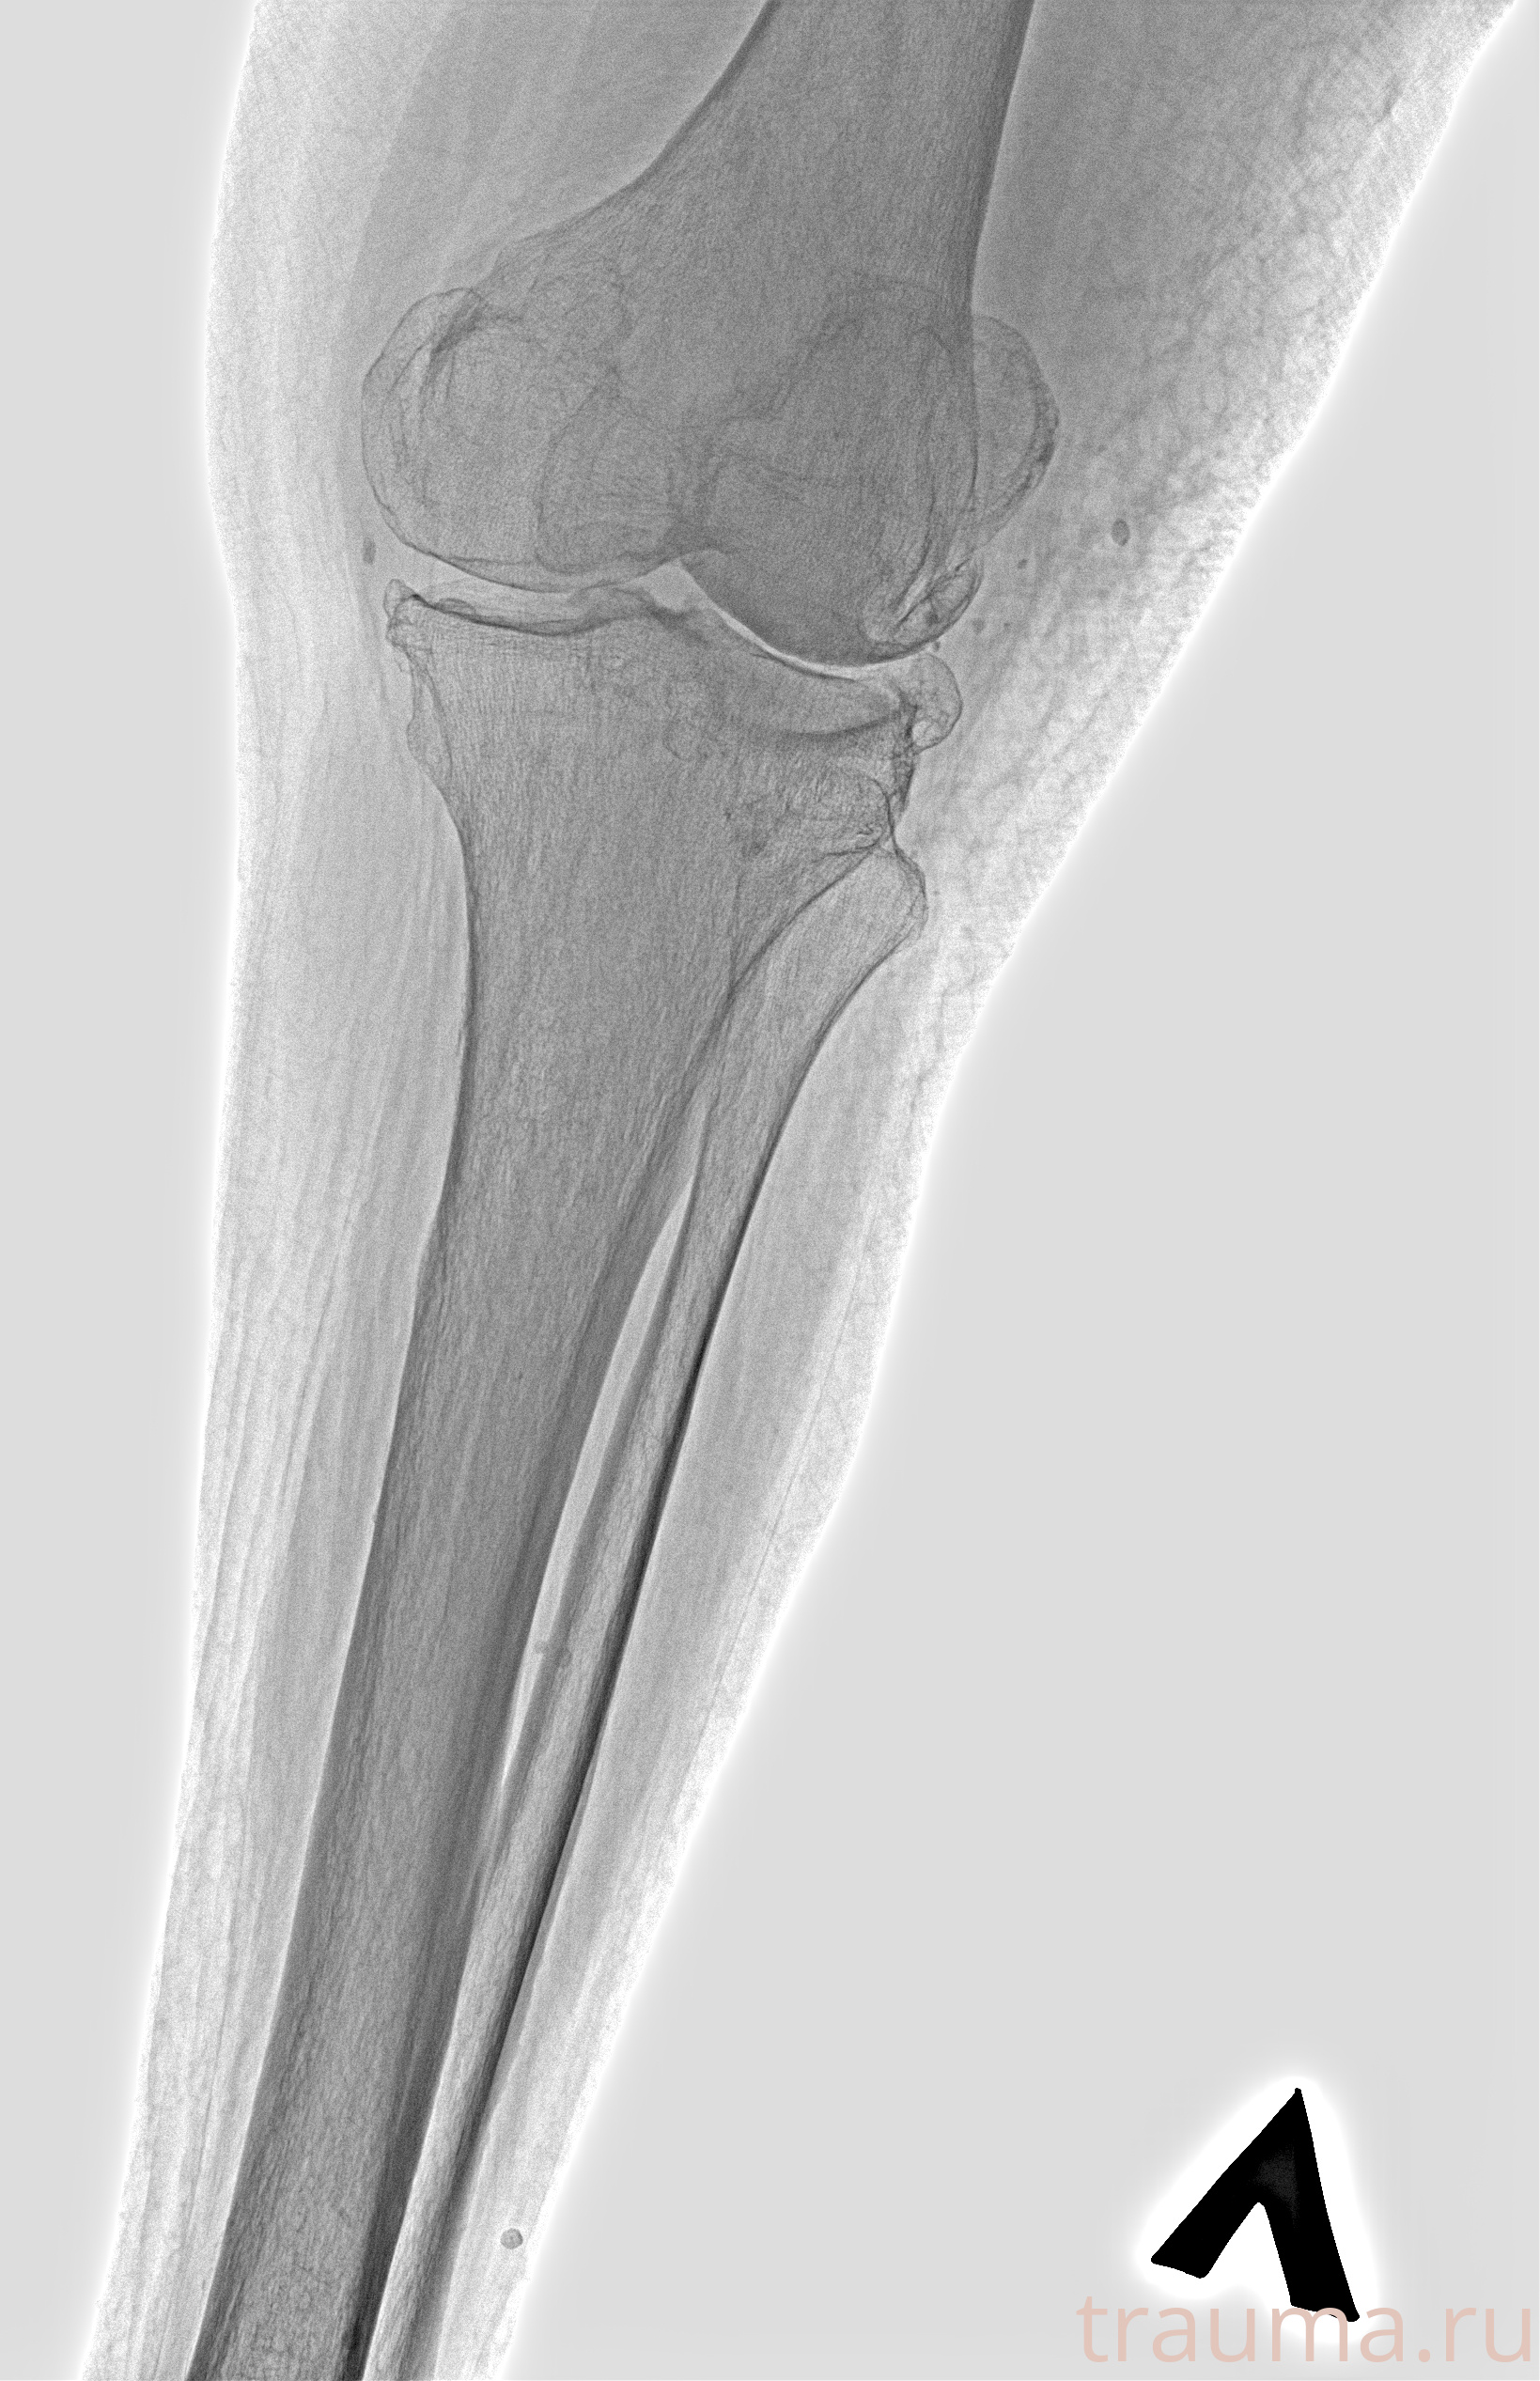

Рентгенограммы

Рентген на дому: по вашему адресу приезжает врач-рентгенолог, травматолог-ортопед с мобильным рентгеновским аппаратом, проводит диагностику травмы или заболевания, делает необходимые рентгенограммы, дает рекомендации по дальнейшему лечению. Получить качественные снимки в домашних условиях возможно благодаря уникальной методике, разработанной МосРентген Центром для института  Склифосовского